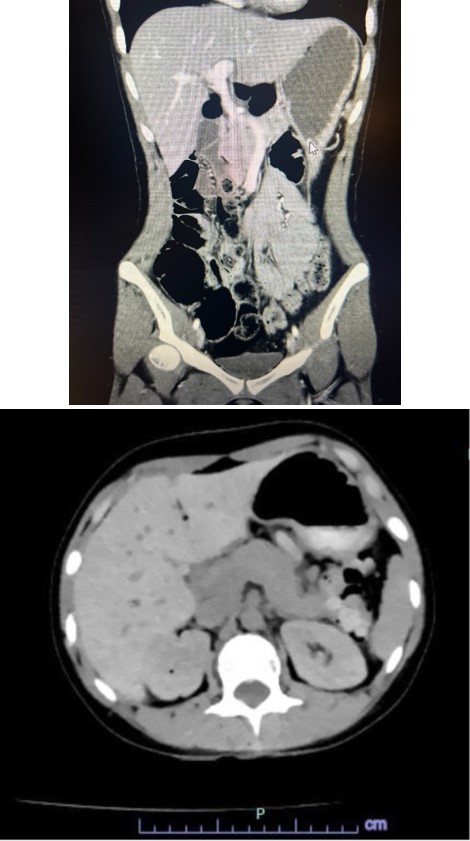

In the ED, labs and imaging studies were done to further assess her acute abdominal complaints. CBC was within normal limits and CMP revealed hyponatremia and hypokalemia. Urine pregnancy test and infectious disease workup were negative. CT abdomen with IV contrast revealed loops of small bowel and mesentery coursing between the celiac artery and portal vein with thinning and stretching of the main portal vein (Figure 1a). These findings suggested evidence of a foramen of Winslow hernia. General surgery was consulted and an operation was initially planned. However. upon repeat evaluation, the patient reported her pain and nausea had completely resolved. Review of systems, vitals, and physical exam at this time were completely negative. Repeat CT revealed oral contrast present throughout the small bowel without abnormal dilation (Figure 1b). These findings suggested spontaneous resolution of the suspected hernia. The plan at this time was to repeat labs and lactate, trial oral intake, and proceed with watchful waiting for recurrence/worsening of symptoms and clinical condition.

Figure 1: (A) CT abdomen suggesting small bowel herniation at FoW, coronal view. (B) CT abdomen suggesting spontaneous reduction of FWH, axial view